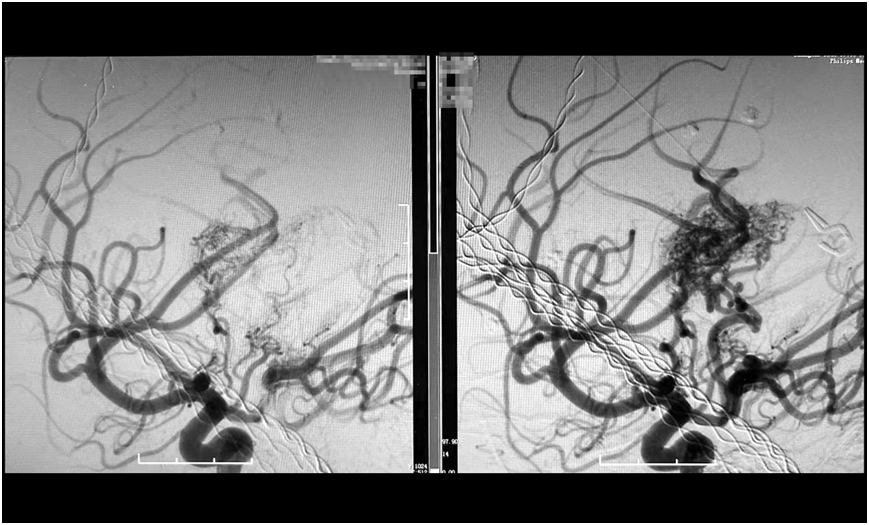

經過數小時的精雕細琢,手術團隊成功栓塞預期目標責任血管。術后造影顯示,假性動脈瘤已完全消失,畸形血管團達到預期栓塞效果,所有正常血管血流保持通暢(mTICI 3級)。

image.png

巨大腦動靜脈畸形(右),被順利栓塞(左)